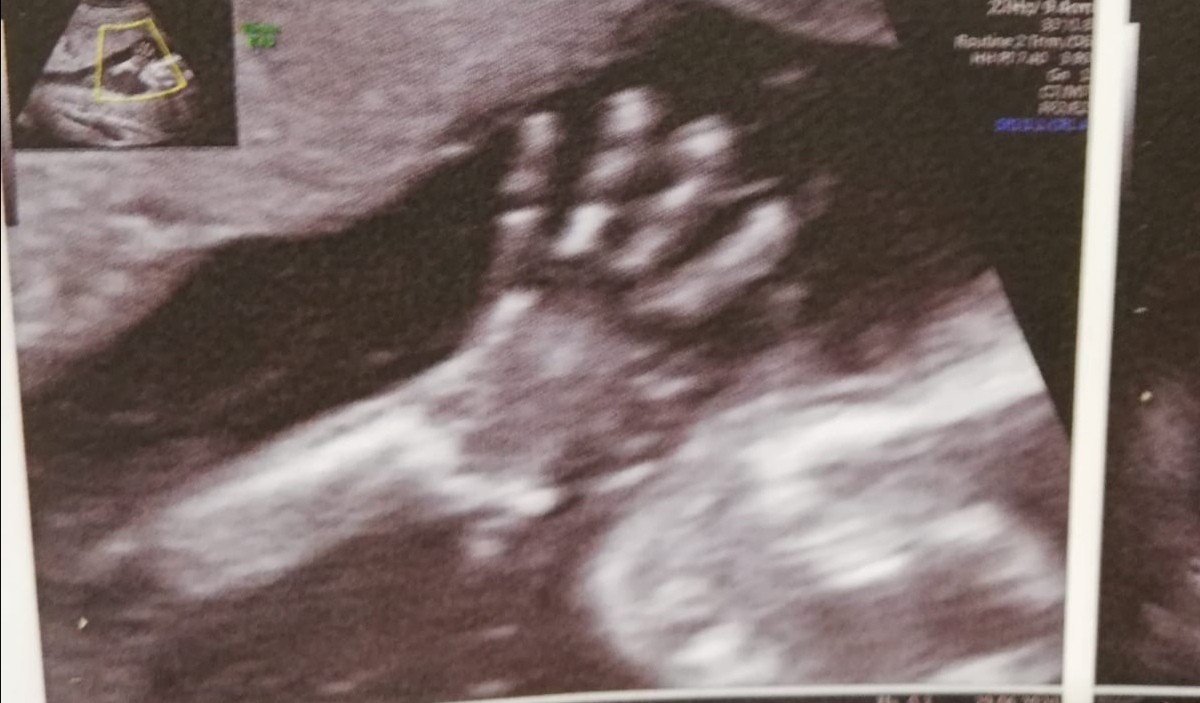

A to zdjęcie kciuka w buzi u mojej kruszynki

A to zdjęcie kciuka w buzi u mojej kruszynki[emoji3531]

A to zdjęcie kciuka w buzi u mojej kruszynki♥